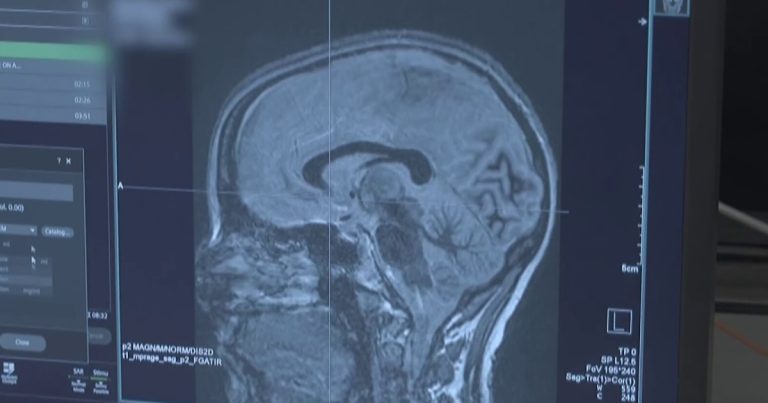

تمنح تقنية جديدة الأمل في مكافحة مرض باركنسون، الذي يصيب أكثر من مليون أمريكي. يقدم الدكتور أكشاي سيال من NBC News تقريرًا عن التحفيز العميق للدماغ ويجري مقابلات مع امرأة تم تشخيصها في الثلاثينيات من عمرها وتقول إن هذه التكنولوجيا تغير حياتها. 14 أبريل 2026